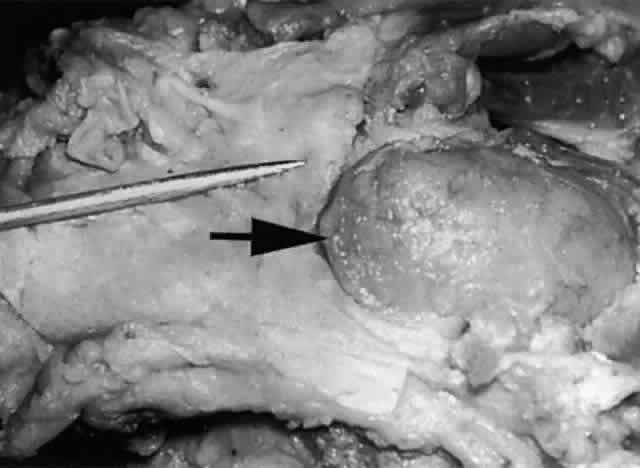

The main lacrimal gland resides in the superotemporal orbit, partially within a shallow bony fossa in the lateral angular process of the frontal bone (fossa glandula lacrimalis). The gland is situated between the eyeball below and the curved orbital wall above, giving it a somewhat compressed and curved shape. It may extend inferiorly to the lateral canthal tendon. The lateral horn of the levator aponeurosis crosses the gland anteriorly, separating it into a larger superior or orbital lobe and a smaller inferior or palpebral lobe (Fig. 2). The division is incomplete because the larger orbital lobe is connected to the smaller palpebral lobe posteriorly by a bridge of glandular tissue, draining tubules, and Müller's muscle, which is attached to the underside of the levator muscle and aponeurosis. The lacrimal gland is surrounded by fibrous tissue that is attached superiorly to the periosteum of the frontal bone and inferiorly to the orbital portion of the zygomatic bone.1

Fig. 2. With the roof and lateral wall of the left orbit removed, this cadaver dissection demonstrates the orbital lobe (black arrow) and the palpebral lobe (white arrow) separated by the lateral horn of the levator aponeurosis (pointer).

These attachments may become attenuated in older persons, allowing the gland to herniate through a weakened orbital septum to give a temporal bulge in the upper eyelid (Fig. 3). The lacrimal gland tissue is usually grayer and pinker than the surrounding yellow adipose tissue.

Fig. 3. Disinsertion or attenuation of the suspensory fibrous attachments of the lacrimal gland will allow the orbital portion to herniate through a weakened orbital septum, producing a temporal bulge in the upper eyelid.